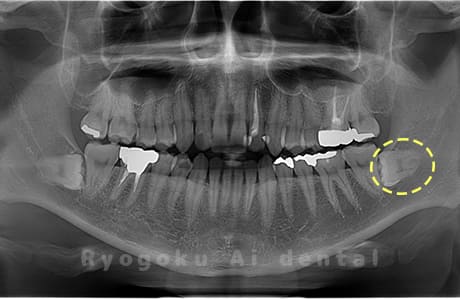

斜めに生えている親知らず

親知らずが斜めに生えて隣の歯にぶつかって圧迫してしまうタイプです。

このタイプが最も多いです。このタイプは虫歯になりやすいだけでなく、隣の歯を圧迫し、咬み合わせや歯並びに影響が出る場合もあるので抜歯をおすすめします。